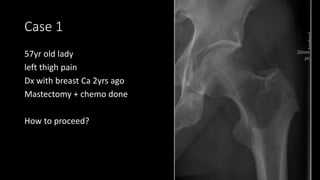

Case 1

57yr old lady

left thigh pain

Dx with breast Ca 2yrs ago

Mastectomy + chemo done

How to proceed?